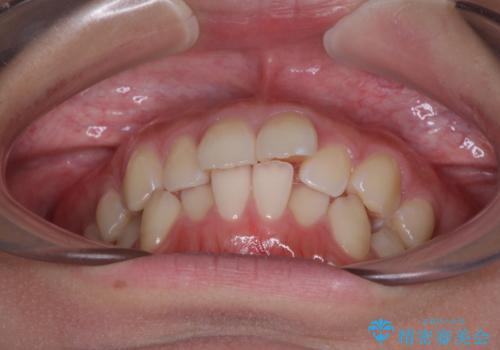

- デコボコを気にして来院された患者様です。

インビザラインでもワイヤー装置でも対応可能でしたが、自己管理の煩わしさの観点から、楽して治療のできるワイヤー装置を選択されました。

抜歯するほどではないものの、やや口元の突出感が気になっていたので、補助装置により上顎臼歯を後方に移動させることで、突出感改善を図ることとしました。